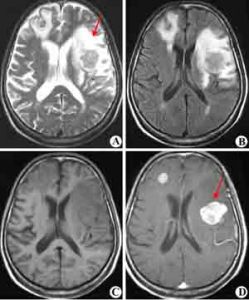

又稱Batson椎靜脈系統,椎靜脈系統的特點是無瓣膜。椎靜脈系統分布在椎腔內外,伸入椎骨內,向上直達顱腦,向前經過椎間孔與其胸腹腰骶等處的奇靜脈屬支及提表,包括皮膚、乳房、外生殖器和肋間靜脈形成廣泛而豐富的側支吻合;因為這組靜脈腔內壓力偏低,血流緩慢,所以患者的咳嗽、打噴嚏、屏氣等都有可能使胸腹腔的壓力暫時升高,此時靜脈系統的癌栓,則有可能通過其位於吻合支而逆流入椎靜脈系統,或者腫瘤受到過度擠壓時,癌細胞可以直接通過椎靜脈系進入脊椎或顱腔。因此,即使在肺內還沒有轉移時,也可以出現顱腦的轉移。由此可見,椎靜脈系統在腫瘤血道轉移中有其特殊的意義。